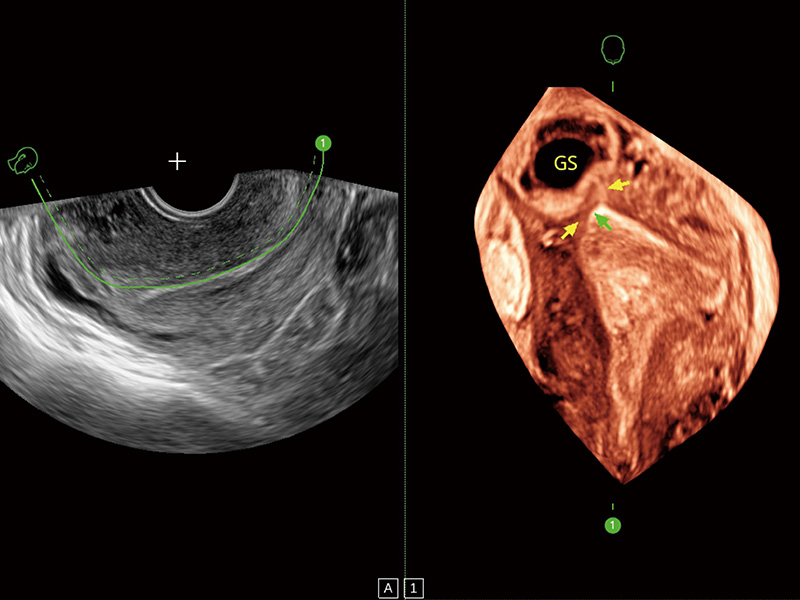

腔内三维成像技术获得显著提升,超大扇角在满足日常基础扫查的同时,支持卵泡自动测量及多种三维渲染模式,为您提供更多的诊断信息,尤其是在子宫畸形的诊断,内膜及肿瘤占位观测中起到了重要的作用。

输卵管间质部妊娠